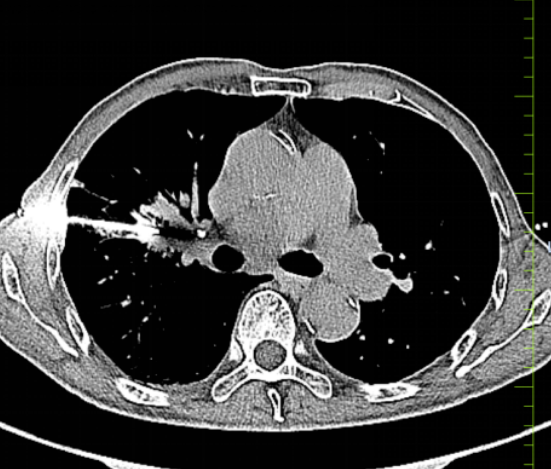

手术当日,在CT精准定位下,穿刺针一次性抵达病灶核心,成功获取足量病理组织,术中无渗血、无血管损伤。术后复查CT显示无出血、气胸等并发症,患者全程清醒,生命体征平稳。

此次手术的成功,体现了医院在复杂高危肺病变微创诊疗领域的技术实力。CT引导下经皮肺穿刺活检是肺部占位诊断的“金标准”,通过术前精准评估、术中精细操作、术后精心护理,不仅实现了安全穿刺、零严重并发症,更为后续明确病理分型及制定靶向、保守等个性化治疗方案提供了关键依据。